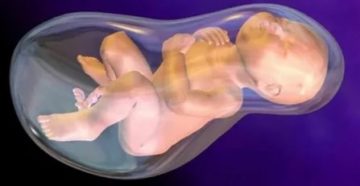

Почему появляется маловодие при беременности и нужно ли его лечить? Маловодие – недостаток околоплодных вод….